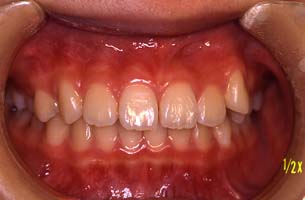

正面 | 矯正前 |

| 120日目 |

| 矯正後(約一年半後) |

右上3番目の歯が八重歯になっています | | |  | | |